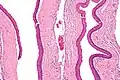

Micrograph of an odontogenic keratocyst. H&E stain.

Odontogenic keratocysts have a diagnostic histological appearance. Under the microscope, OKCs vaguely resemble keratinized squamous epithelium;[15] however, they lack rete ridges and often have an artifactual separation from their basement membrane.[2]

The fibrous wall of the cyst is usually thin and uninflamed. The epithelial lining is thin with even thickness and parakeratinised with columnar cells in the basal layer which have focal reverse polarisation (nuclei are on the opposite pole of the cell).[13] The basal cells are an indication of the odontogenic origin as they resemble pre-ameloblasts. The epithelium can separate from the wall, resulting in islands of epithelium. These can go on to form 'satellite' or 'daughter' cysts, leading to an overall multilocular cyst.[10] Presence of daughter cysts is particularly seen in those with NBCCS.[13] Inflamed cysts show hyperplastic epithelium which is no longer characteristic of OKCs and can have resemblance to radicular cysts instead. Due to areas of focal inflammation, a larger biopsy is required for correct diagnosis of odontogenic keratocysts.[10]